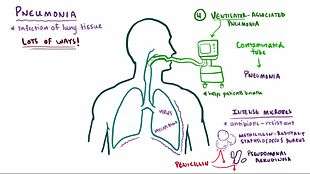

Pneumonia is an inflammatory condition of the lung affecting primarily the microscopic air sacs known as alveoli.[2][3] Typical signs and symptoms include a varying severity and combination of productive or dry cough, chest pain, fever, and trouble breathing, depending on the underlying cause.[4]

Pneumonia is usually caused by infection with viruses or bacteria and less commonly by other microorganisms, certain medications and conditions such as autoimmune diseases.[2][5] Risk factors include other lung diseases such as cystic fibrosis, COPD, and asthma, diabetes, heart failure, a history of smoking, a poor ability to cough such as following a stroke, or a weak immune system.[6] Diagnosis is often based on the symptoms and physical examination. Chest X-ray, blood tests, and culture of the sputum may help confirm the diagnosis.[7] The disease may be classified by where it was acquired with community, hospital, or health care associated pneumonia.[8]

Cause

Pneumonia is due to infections caused primarily by bacteria or viruses and less commonly by fungi and parasites. Although there are more than 100 strains of infectious agents identified, only a few are responsible for the majority of the cases. Mixed infections with both viruses and bacteria may occur in up to 45% of infections in children and 15% of infections in adults.[12] A causative agent may not be isolated in approximately half of cases despite careful testing.[16]

Bacteria

Bacteria are the most common cause of community-acquired pneumonia (CAP), with Streptococcus pneumoniae isolated in nearly 50% of cases.[29][30] Other commonly isolated bacteria include Haemophilus influenzae in 20%, Chlamydophila pneumoniae in 13%, and Mycoplasma pneumoniae in 3% of cases;[29] Staphylococcus aureus; Moraxella catarrhalis; Legionella pneumophila and Gram-negative bacilli.[16] A number of drug-resistant versions of the above infections are becoming more common, including drug-resistant Streptococcus pneumoniae (DRSP) and methicillin-resistant Staphylococcus aureus (MRSA).[20]

The spreading of organisms is facilitated when risk factors are present.[16] Alcoholism is associated with Streptococcus pneumoniae, anaerobic organisms, and Mycobacterium tuberculosis; smoking facilitates the effects of Streptococcus pneumoniae, Haemophilus influenzae, Moraxella catarrhalis, and Legionella pneumophila. Exposure to birds is associated with Chlamydia psittaci; farm animals with Coxiella burnetti; aspiration of stomach contents with anaerobic organisms; and cystic fibrosis with Pseudomonas aeruginosa and Staphylococcus aureus.[16] Streptococcus pneumoniae is more common in the winter,[16] and should be suspected in persons aspirating a large amount anaerobic organisms.[20]

Classification

Pneumonitis refers to lung inflammation; pneumonia refers to pneumonitis, usually due to infection but sometimes non-infectious, that has the additional feature of pulmonary consolidation.[53] Pneumonia is most commonly classified by where or how it was acquired: community-acquired, aspiration, healthcare-associated, hospital-acquired, and ventilator-associated pneumonia.[29] It may also be classified by the area of lung affected: lobar pneumonia, bronchial pneumonia and acute interstitial pneumonia;[29] or by the causative organism.[54] Pneumonia in children may additionally be classified based on signs and symptoms as non-severe, severe, or very severe.[55]

The setting in which pneumonia develops is important to treatment,[56][57] as it correlates to which pathogens are likely suspects,[56] which mechanisms are likely, which antibiotics are likely to work or fail,[56] and which complications can be expected based on the person's health status.

Community

Community-acquired pneumonia (CAP) is acquired in the community,[56][57] outside of health care facilities. Compared with health care–associated pneumonia, it is less likely to involve multidrug-resistant bacteria. Although the latter are no longer rare in CAP,[56] they are still less likely.

Healthcare

Health care–associated pneumonia (HCAP) is an infection associated with recent exposure to the health care system,[56] including hospital, outpatient clinic, nursing home, dialysis center, chemotherapy treatment, or home care.[57]

Hospital

Hospital-acquired pneumonia is acquired in a hospital[56] (specifically, pneumonia that occurs 48 hours or more after admission, which was not incubating at the time of admission[57]), and as such is likely to involve hospital-acquired infections, with higher risk of multidrug-resistant pathogens. Also, because hospital patients are often ill (which is why they are present in the hospital), comorbidities are an issue.

Ventilator

Ventilator-associated pneumonia occurs in people breathing with the help of mechanical ventilation[56] (specifically, it is pneumonia that arises more than 48 to 72 hours after endotracheal intubation[57]). Like any medical device, ventilators involve some risk of infection because of how difficult it is to prevent bacteria from colonizing the internal parts and surfaces, even with diligent cleaning. People who need ventilators typically are rather ill, to begin with, so a superimposed pneumonia is not always easily managed. Immunodeficiency may be involved because of poor nutritional status and whichever disorders are comorbid.